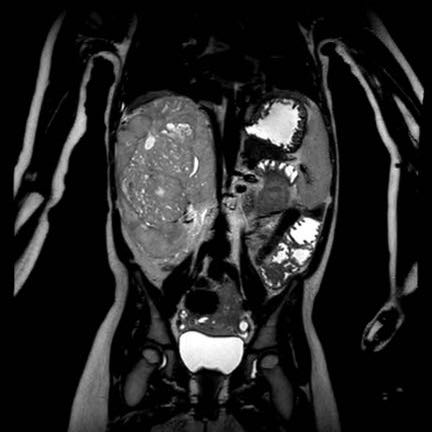

Ca lâm sàng 1

Hình ảnh chuỗi xung T2W mặt phẳng coronal cho thấy một khối u không đồng nhất ở thận trái với các thành phần nang nhỏ.

Khối u ngấm thuốc kém hơn so với phần nhu mô thận bình thường còn lại ở ngoại vi.

Các thành phần đặc của khối u cho thấy hạn chế khuếch tán rõ rệt (mũi tên).

Đây là u Wilms ở bé trai năm tuổi. Hóa trị tiền phẫu được thực hiện theo phác đồ Umbrella của SIOP-RTSG, sau đó tiến hành cắt thận.